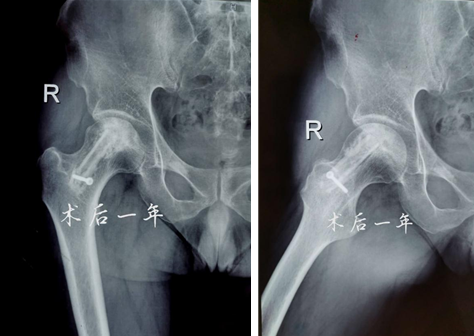

术后一年

术后12个月和24个月,患者来院复查,影像片子显示患者右侧股骨头髋臼平整光滑,股骨头圆润光滑,股骨头内骨小梁密度均匀,已恢复至正常股骨头状态,几乎与正常人股骨头无异。患者随访时说:“来医院之前,我独立行走都困难,短短几米的距离,我可能要花费三四分钟才能走完。手术之后,我不仅可以健步如飞,还能做下蹲等动作,也不必担心重体力劳动导致股骨头无法承受的问题,这个手术真的是太好了,不仅救了我,也救了我一家人……”